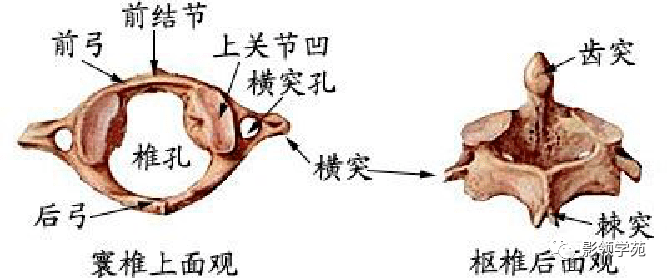

骨骼系统

骨骼系统